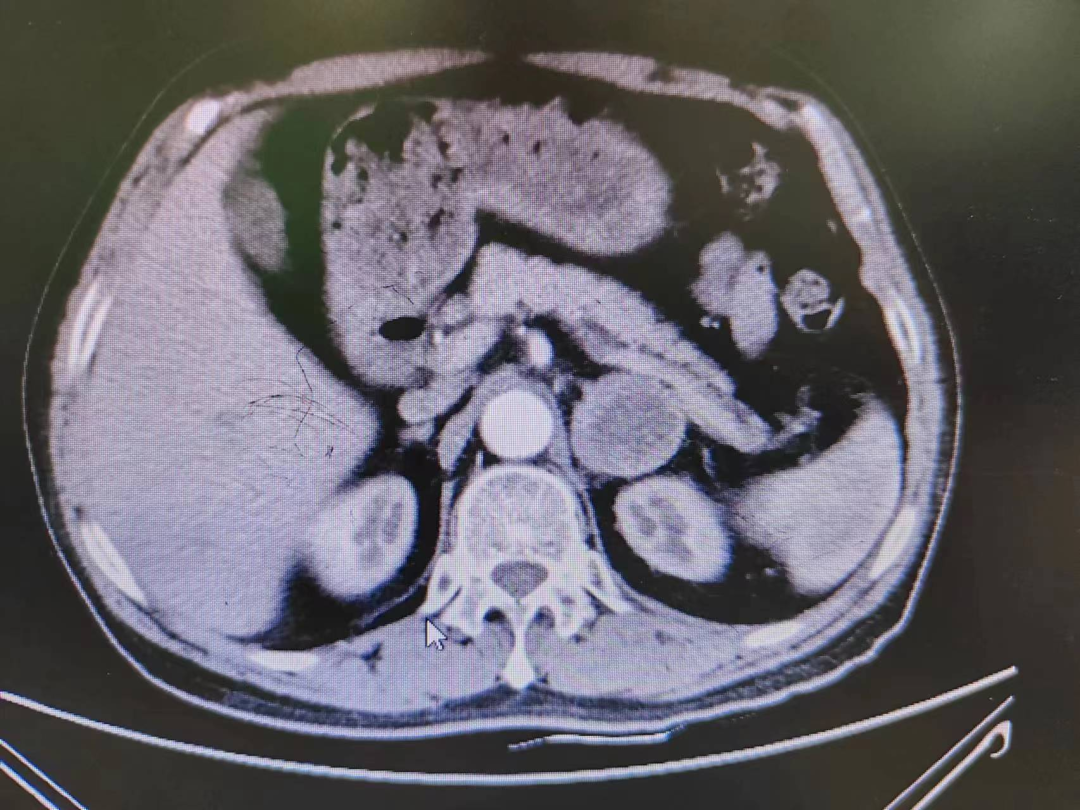

患者熊XX,67歲,因發(fā)現(xiàn)頭暈、頭痛曾多次于外院就診,到新橋醫(yī)院就診完善腎上腺CT考慮嗜鉻細(xì)胞瘤,既往有高血壓病史3年,血壓更高達(dá)230/120mmHg。我院高新區(qū)院區(qū)開診后,患者慕名而來(lái)。術(shù)前積極完善血尿兒茶酚胺代謝產(chǎn)物(MNS)均明顯升高,患者于我院高新區(qū)院區(qū)及江南院區(qū)泌尿外科積極控制血壓、心率、血糖,術(shù)前充分?jǐn)U容。

因腫瘤位置位于腎蒂周圍,術(shù)中觸碰腫瘤導(dǎo)致血壓明顯升高,血壓波動(dòng)較大,腫瘤表面血供豐富,不僅需要手術(shù)醫(yī)生豐富的臨床經(jīng)驗(yàn)和高超的技術(shù)水平,也是對(duì)醫(yī)生心理素質(zhì)、勇氣和毅力的嚴(yán)峻考驗(yàn)。

經(jīng)過(guò)泌尿外科醫(yī)師全體討論,在進(jìn)行術(shù)前準(zhǔn)備2-3周后,再次請(qǐng)多學(xué)科討論評(píng)估手術(shù)風(fēng)險(xiǎn),并與患者及家屬充分溝通后于6月30日行腹腔鏡下左側(cè)腎上腺嗜鉻細(xì)胞瘤切除術(shù)。手術(shù)在陳勇主任醫(yī)師的指導(dǎo)下,由孫偉副主任醫(yī)師主刀及王傳麟醫(yī)師完成,術(shù)中見腫瘤與腎蒂血管周圍粘連緊密,與腎動(dòng)脈、腎靜脈分界不清,稍有不慎,可能損傷腎蒂血管可能需要行腎切除術(shù),且分離腫瘤過(guò)程中血壓波動(dòng)較大。但在孫偉精準(zhǔn)操作及分離下,與麻醉醫(yī)生和手術(shù)護(hù)士團(tuán)隊(duì)密切配合,經(jīng)過(guò)2小時(shí)的手術(shù),順利切除嗜鉻細(xì)胞瘤,并保護(hù)好腎臟血管及周圍組織。術(shù)后患者順利出院,術(shù)后血壓及血糖控制良好。